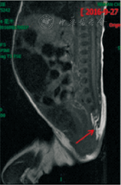

例1,女,7 d,因"反复呕吐"就诊。入院查体:体温36.5 ℃,面容特殊(图1A),足月小样儿,神志清楚,反应可,皮肤颜色红润,弹性正常;双肺呼吸音清,未闻及干湿性啰音;心率144次/min,心音有力,心脏各听诊区未闻及杂音;四肢未见异常,活动无受限,视不追物,腹部外形膨隆,以上腹部为主,胃型无,肠型无,全腹柔软(图1B);肝肋下1 cm可触及,质软。神经系统查体:肌张力正常,吸吮反射、双手握持反射以及拥抱反射均减弱。进一步查体发现患儿肛门狭窄,肠道造影提示中肠旋转不良;疑似先天性巨结肠;心脏彩超提示卵圆孔未闭或房间隔缺损;头颅超声提示颅内出血,骶尾椎磁共振成像(MRI)示脊髓栓系,骶尾椎发育畸形,见图2。患儿父母身体健康,非近亲结婚,且双方家庭均无类似疾病家族史。患儿母亲34岁,孕40周,自然分娩;患儿系第4胎,第2产,患儿有一哥哥,表型正常;其余2胎为死胎或死产。

例2,女,1岁3个月,因"发育迟缓"就诊。入院查体:体温36.8 ℃,神志清醒,面容异常(图1C);皮肤色泽正常,反应可;双肺呼吸运动对称,呼吸音听诊正常,未闻及啰音;心脏各听诊区未闻及杂音;四肢未见异常,大动作及精细动作均落后同龄儿童,Gesell发育量表显示,适应性59,大运动46,精细动作53,语言59,个人社交58。患儿先天性右眼上睑下垂,眼神交流差。家长口述:患儿出生15 d右眼睁开,胀气严重,排便困难。神经系统检查:肌张力未见明显异常,生理反射正常,Babinski征阴性,Brudzinkski征阴性。进一步查体发现患儿肛门狭窄;外院脊椎MRI示隐性脊椎裂的症状(图2)。头颅MRI未见异常。患儿系第1胎,第1产,足月自然分娩,父母身体健康,非近亲结婚,且双方家庭均无类似疾病家族史。